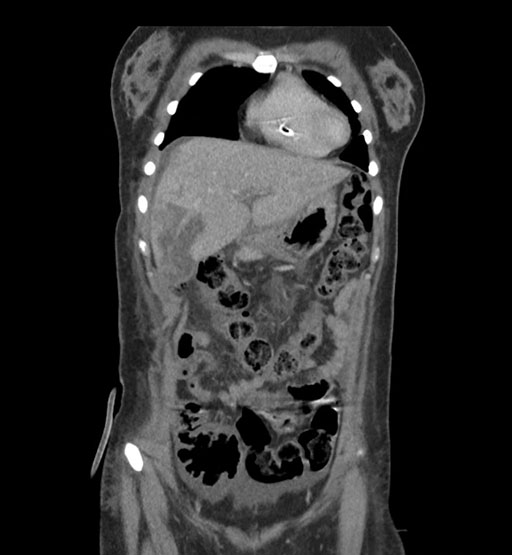

Imaging Analysis

Look through the patient's CT scan to identify any areas of concern for the necessary procedure.

Coronal Arterial

Coronal Venous

Based on initial findings, which issue(s) would you be most concerned about?